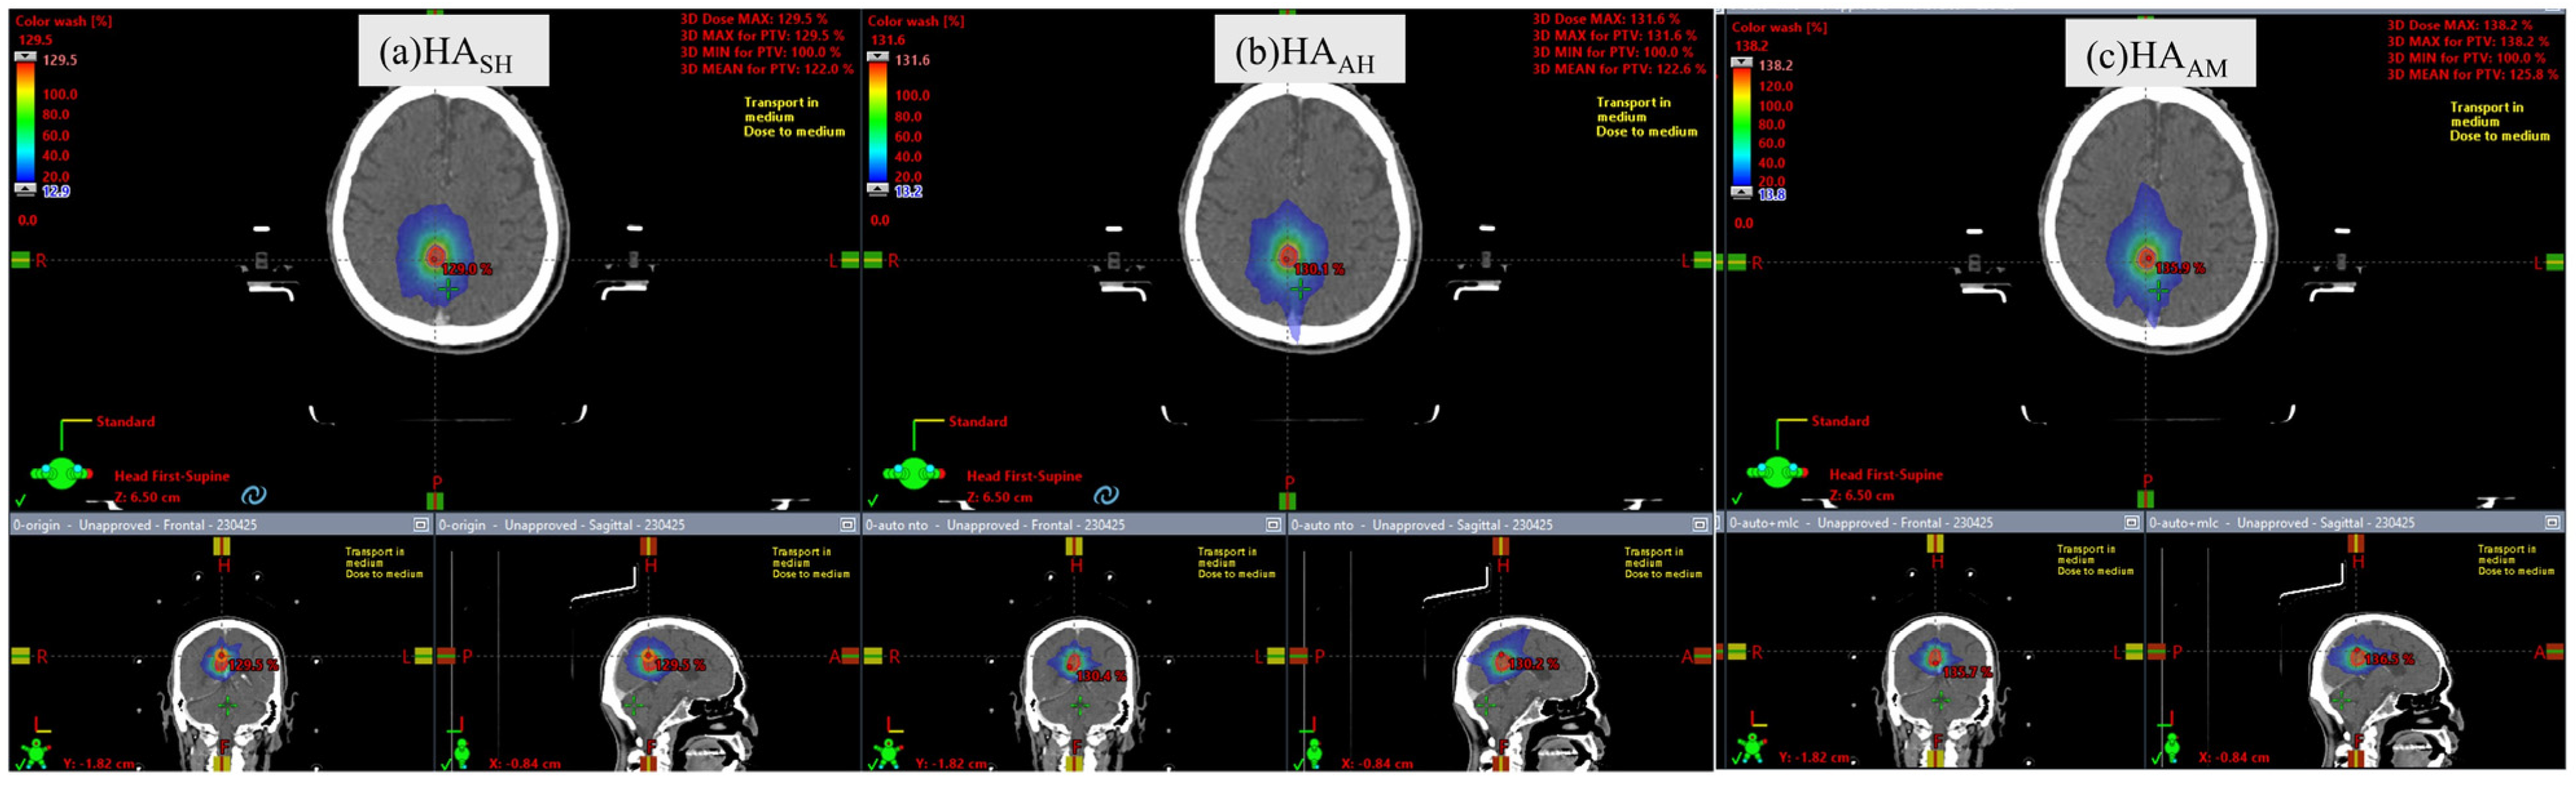

2.5. Treatment Planning

2.7. Statistical Analysis of HASH, HAAH, and HAAM Plans

3.1. Plan Comparison of HASH and HAAH

3.2. Plan Comparison of HAAH and HAAM